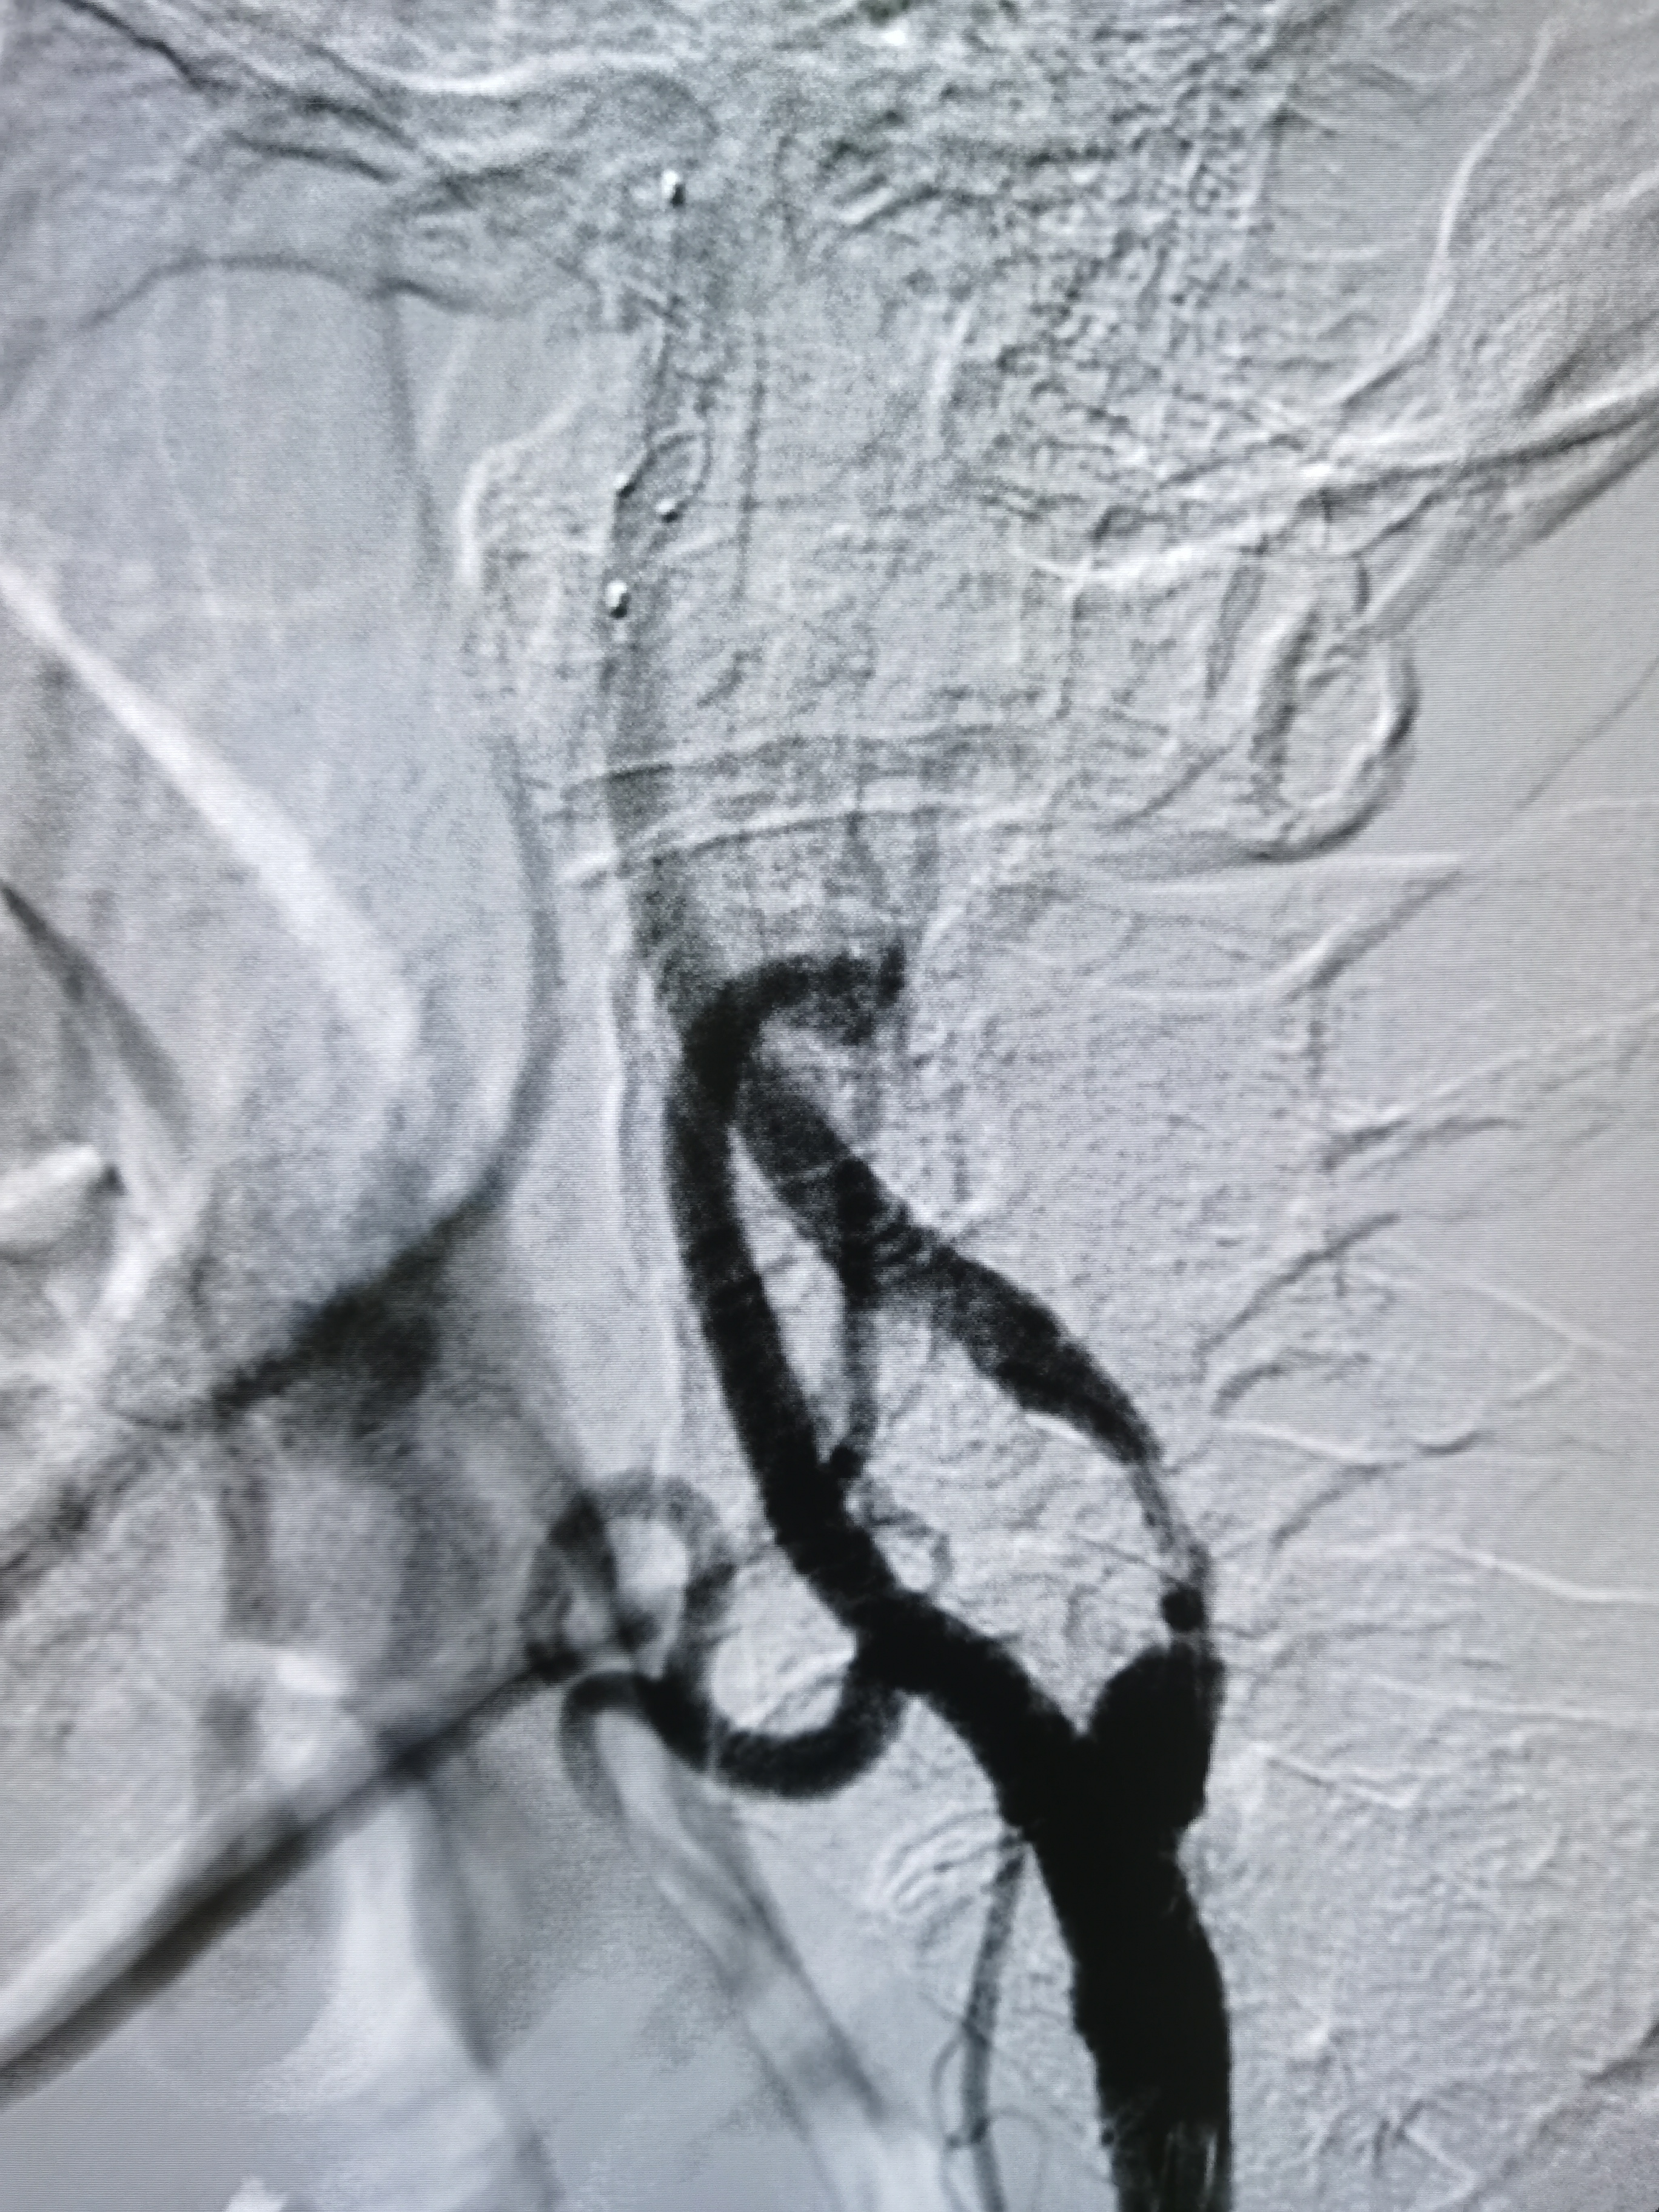

8F导引导管到位后明确工作位。

微导丝顺利通过病变后交换入远端保护伞

4/30球囊预扩后狭窄改善

9/40支架定位

支架释放后狭窄解除